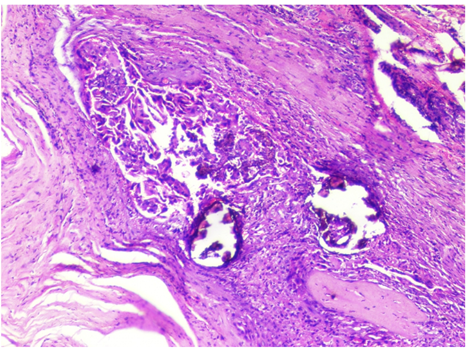

A 47 year old male came to the Surgical Clinics with complaints of progressively increasing midline neck swelling for the last 4 years. He had no history of pain, dysphasia, hoarseness of voice, fever, loss of appetite and loss of weight. He also had no history of any systemic illness and family history. On examination, a well-defined cystic, non tender, swelling, 8 cm×6 cm in size was seen in the mid of the neck. The overlying skin appeared to be normal with no signs of sinus or fistula. The mass was fixed to the underlying structures, was compressible, non-pulsatile, non-fluctuant and moving with deglutition. No neck nodes were palpable. A provisional diagnosis of a thyroglossal cyst was given. Fine needle aspiration cytology showed features of a cystic lesion. X‑ray chest was normal. On ultrasonography, a large lobulated cystic mass with hyper and hypoechoeic areas with focal calcification was seen. There was no abnormality detected in routine hematologic and urine investigations. Surgical excision of the cystic swelling with sistrunk’s procedure was performed. Grossly, the specimen was 10.4cm×6cm×3.8 cm in size, with multinodular and well capsulated external surface. Cut section showed a multiloculated cystic swelling with foci of solid grey white areas with focal papillary excrescences. Microscopic examination showed a multiloculated cystic lesion with variable sized thyroid follicular epithelial cells and foci of calcification. Focal areas of cellular atypia was noted within tumor cells exhibiting ground glass nuclei Figure 1 & 2. Immunohistochemical staining showed diffuse moderate intensity cytoplasmic positivity of Pan Cytokeratin Figure 3. A histopathologic impression of papillary carcinoma of thyroid in a thyroglossal cyst was made. Postoperative period was uneventful and our patient was absolutely all right. 50 Gy of Co-60 radiotherapy and adjuvant chemotherapy with Cisplatin 50mg/m2x6 cycles was administered. Our patient is doing well after 12 months of follow up.

Figure 1 Microscopic examination shows a multiloculated cystic lesion with variable sized thyroid follicular epithelial cells and foci of calcification. Focal areas of cellular a typical was noted within tumor cells exhibiting ground glass nuclei. Hematoxylin and Eosin x10X.